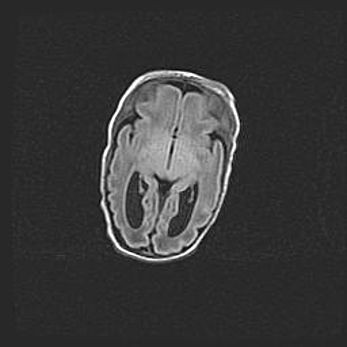

Открытая гидроцефалия.

Возраст: 9 месяцев 12 дней

Вес: 6800 г

Пол: мужской

Окружность головы: 41,5 см

Срок гестации: 28 недель

Гидроцефалия головного мозга у новорожденных имеет характерный признак: опережающий рост окружности головы приводит к визуально хорошо определяемой гидроцефальной форме сильно увеличенного в объёме черепа. Детские неврологи определяют следующие симптомы гидроцефалии у грудничков: выбухающий напряжённый родничок, частое запрокидывание головы, смещение глазных яблок к низу.